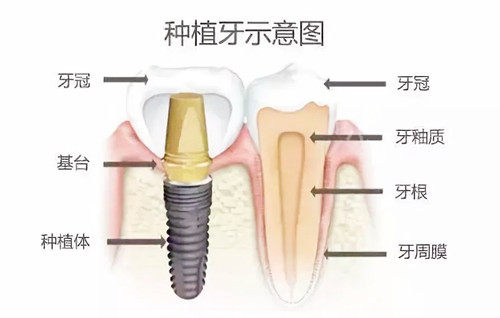

濮阳光华口腔拥有一支正规的医疗团队,包括经验充足的口腔医生和护士。他们不仅具备扎实的医学知识和娴熟的医疗技术,还能够为患者提供贴心、周到的服务。医院在牙齿矫正、种植牙、牙齿修复等方面技术成熟,能够满足不同患者的口腔健康需求。此外,医院还配备了新型的医疗设备,如CBCT三维影像系统、智能化全景机等,为患者的诊断和治疗提供了有力确保。